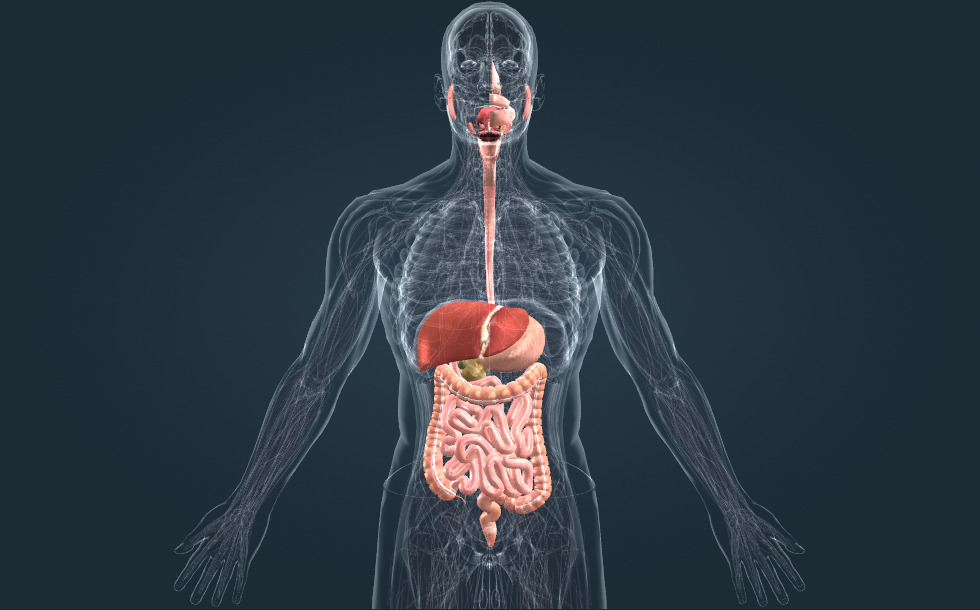

Virškinamasis traktas

- skrandis - Šiame organe pasisavinami proteinai. Skrandžio sultyse gausu rūgščių.

- plonoji žarna - Šiame organe virškinami angliavandeniai ir riebalai. Čia sugeriamos suvirškintos maistingosios medžiagos.

- gaubtinė žarna - Čia virškinamas vanduo ir mineralai. Jos bakterinė flora gamina vitaminus K ir B.

- tiesioji žarna

- kepenys - Jos atlieka svarbų vaidmenį detoksikacijos procese bei gamina tulžį, dalyvaujančią riebalų virškinime.

- kasa - Ji gamina kasos sultis, kurių dėka plonojoje žarnoje pasisavinami riebalai, angliavandeniai ir baltymai. Ji taip pat išskiria insulino hormoną, kuris mažina gliukozės kiekį kraujyje.

- stemplė

- burnos ertmė

- tulžies pūslė - A hollow, pear-shaped organ where bile is stored temporarily. While stored here, the bile becomes concentrated.

Virškinamasis traktas atsakingas už maistingųjų medžiagų virškinimą ir pasisavinimą. Burnoje maistą sutraiško dantys; prasideda angliavandenių pasisavinimas. Baltymai pasisavinami rūgščių kupiname skrandyje. Plonojoje žarnoje absorbuojami visi trys maistingųjų medžiagų tipai, t.y., proteinai, angliavandeniai ir riebalai. Kasos sultys, gaminamos kasoje ir turinčios savyje virškinimo enzimų, ten išvalomos - taip pat kaip ir kepenų gaminama tulžis, dalyvaujanti riebalų pasisavinime. Gaubtinė žarna sugeria vandenį ir mineralus; jos bakterinė flora gamina vitaminus.

Virškinamasis traktas atsakingas už maistingųjų medžiagų virškinimą ir pasisavinimą. Burnoje maistą sutraiško dantys; prasideda angliavandenių pasisavinimas. Baltymai pasisavinami rūgščių kupiname skrandyje. Plonojoje žarnoje absorbuojami visi trys maistingųjų medžiagų tipai, t.y., proteinai, angliavandeniai ir riebalai. Kasos sultys, gaminamos kasoje ir turinčios savyje virškinimo enzimų, ten išvalomos - taip pat kaip ir kepenų gaminama tulžis, dalyvaujanti riebalų pasisavinime. Gaubtinė žarna sugeria vandenį ir mineralus; jos bakterinė flora gamina vitaminus.